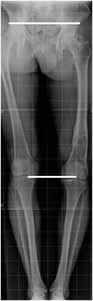

Fig 103. Longitud de extremidades.

A y B: Rx simple. Medición de las extremidades. En el fémur desde el borde superior de la cabeza femoral, hasta el borde inferior del cóndilo medial y en la pierna desde la eminencia intercondilea, hasta el borde inferior de la tibia.